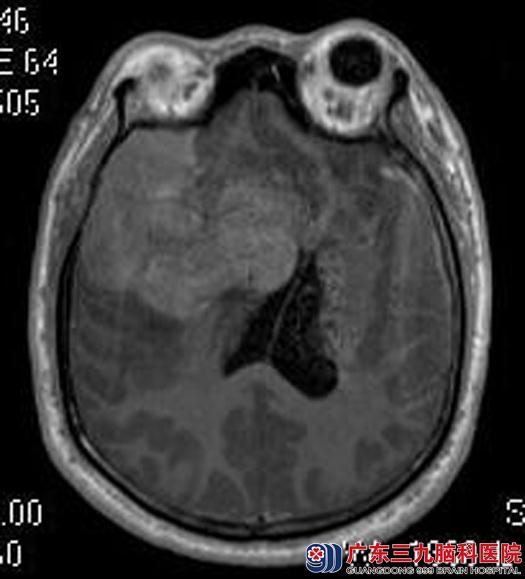

住院在广东三九脑科医院综合神经外科,头颅MR检查提示:右侧额颞部大脑凸面示一不规则巨大团块状占位性病变,大小约为7.8cm×6.2cm×7.8cm,考虑脑膜瘤可能、邻近颅骨受侵犯。

完善术前检查后,由鲁明主任主刀,在全麻下行右侧额颞部巨大脑膜瘤切除术,术前导航定位肿瘤范围,显微镜下见肿瘤质地韧,血供丰富,以电磁刀辅助分块全切肿瘤,手术顺利。术后邝先生恢复很好,已康复出院。病理结果:不典型脑膜瘤 WHO II级。